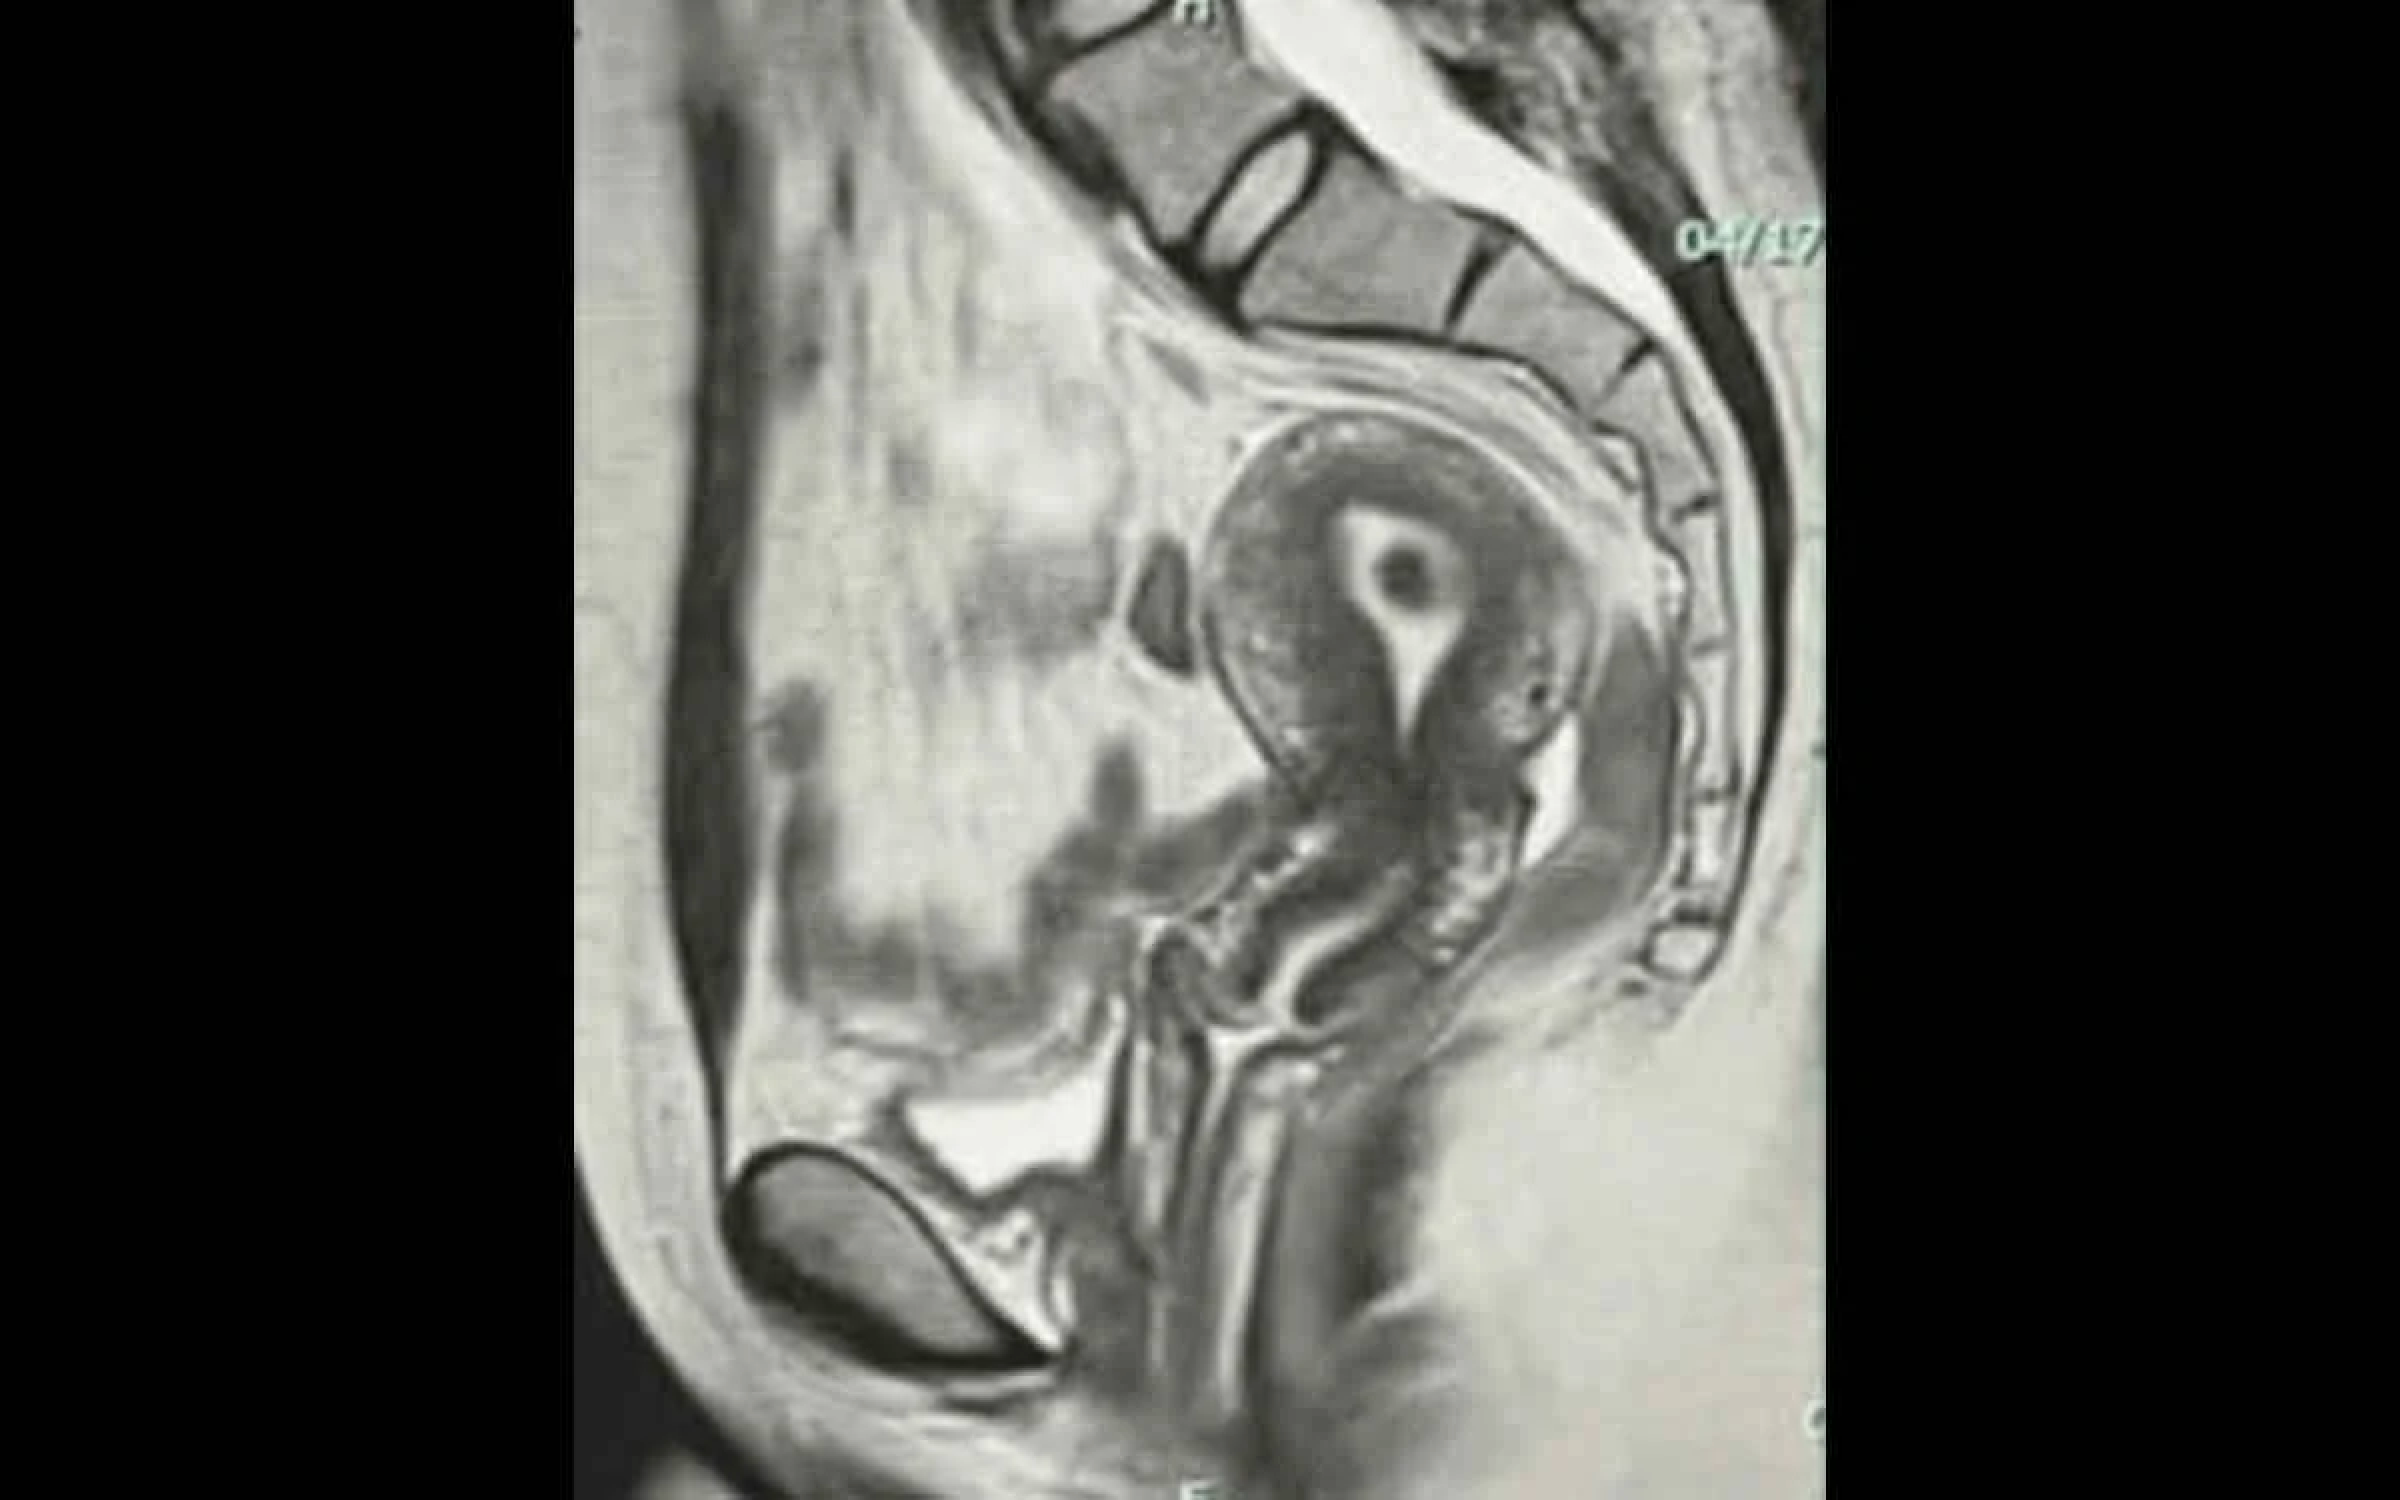

At The Women’s Imaging Center, your pelvic MRI is in good hands. As specialists in body imaging for women, including breast, gynecologic, abdominal, thyroid, pelvic, and bone, our fellowship-trained radiologists are experts at interpreting MRIs. We invest in state-of-the-art technology and take a comprehensive approach to care, from screening to diagnosis to treatment, ensuring every aspect of your health receives expert attention.